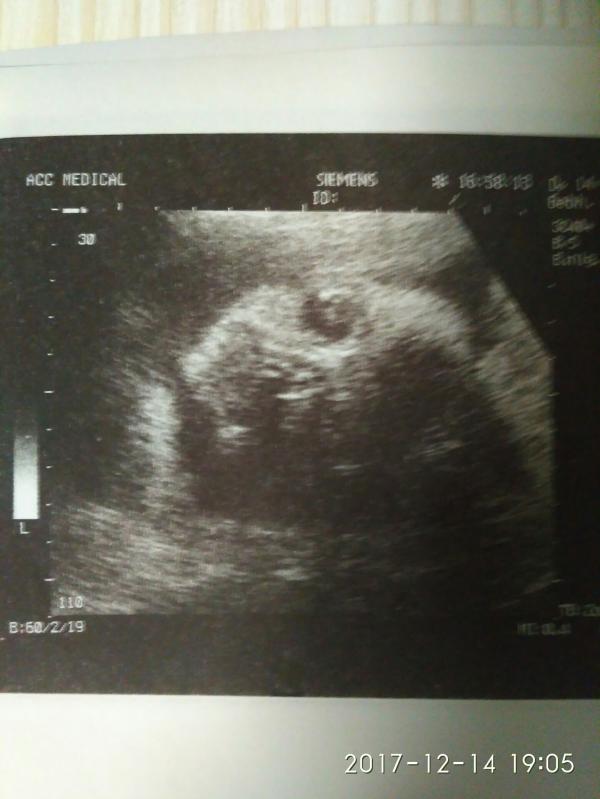

Была сегодня на плановом УЗИ, виделась со своей девочкой😍😘, эмоции переполняют. Все показатели в норме, вес 1460. А сколько ваши детки весили в 30 недель? Единственное, что сидит на попе, но сказали ещё есть время перевернуться. У кого так было? Перевернулись ли детки? И плацента 1 степени, сказали, что это нормально. Сделали мне фото пирожка😂, чтобы мама больше не сомневалась, что там доця))). Как же я люблю свою девочку😘😘😘, уже не могу дождаться встречи.

@begemotik91 😂😂😂 пирожок, пирожок! На экране очень хорошо видела)